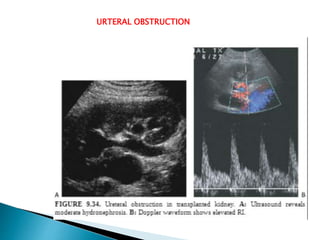

URTERAL OBSTRUCTION